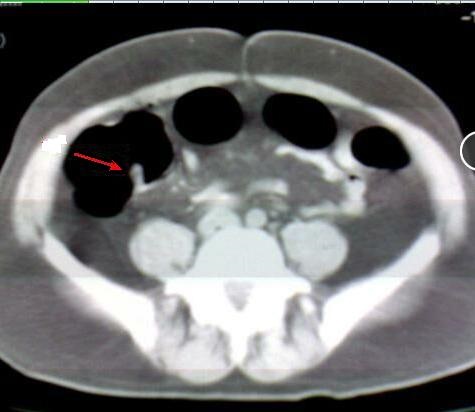

Aspect radiologique polypoide multiple du

colon . Image du polyp ét tré nombreuse et s'etendre

le long du colon ascendant , transverse et

descendant . Image radilologique TDM a lavement

baryte du polyp dans ce cas est multiple a

hypo-dense et s'etendre le long de arcade colique .

Maladie polypoide du colon |

Même cas en coupe TDM

axiale a travers L2, L3 . Image du polyp dans ce cas

est multiple polypoide a hypodense s'etendre

le long du colon transverse . Image

radiologique TDM du colon avec lavement opaque du

colon . |